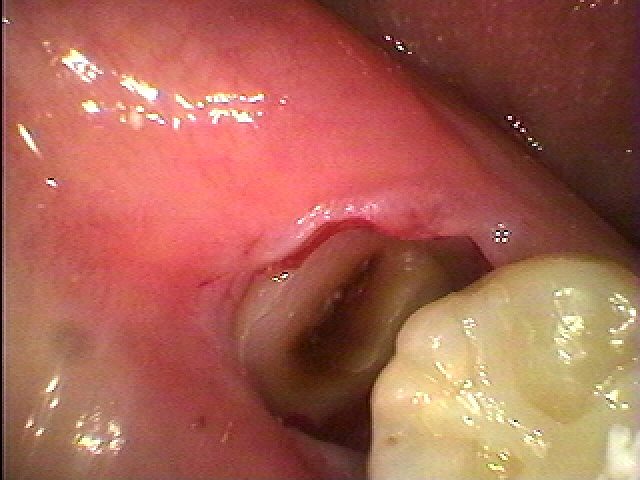

根部分を取り出します

縫合して終了となります

根部分を取り出します

縫合して終了となります